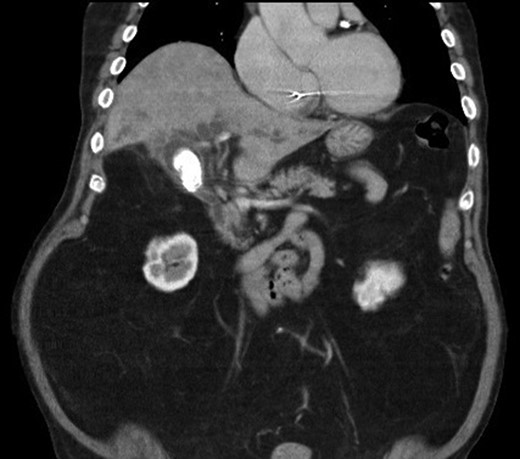

We report a case of a 67-year-old man, who presented with fever, chills and jaundice to a local district hospital. He had a temperature of 39°C and new-onset atrial fibrillation. Examination of the abdomen showed no peritoneal signs. Blood biochemistry demonstrated leukocytosis and abnormal liver function tests: bilirubin 75 μmol/L, alkaline phosphatase 1018 unit/L, alanine transaminase 177 unit/L. Ultrasound scan showed a 3 cm gallstone without common bile duct dilatation. However, computed tomography of abdomen revealed a gallstone eroding into the CHD, causing intrahepatic ductal dilatation (Fig. 1). The diagnosis of type II Mirizzi syndrome was confirmed by endoscopic retrograde cholangiopancreatography (ERCP), where cholangiogram demonstrated a gallstone fistulating into the CHD (Fig. 2). Biliary stent was inserted and intravenous antibiotics were given to tie over this acute episode of cholangitis.

Cholangiogram demonstrating filling defects at the common hepatic duct.